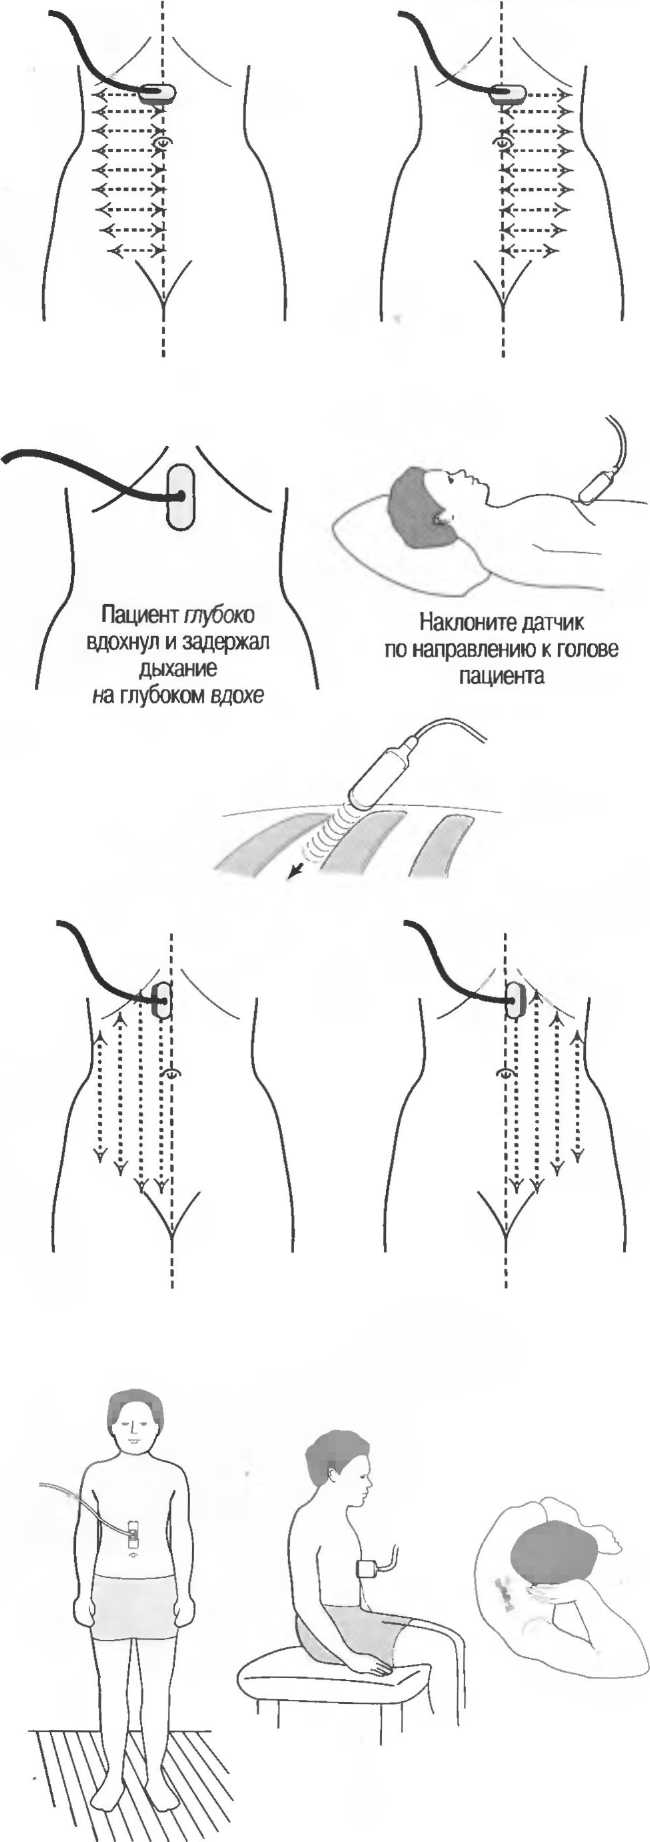

Газ отражает ультразвук и экранирует ткани, расположенные сзади, в результате преломления и акустической тени от газа. Газ в кишечнике может экранировать печень, поджелудочную железу, парааортальные лимфоузлы, матку, яичники. Иногда удается сместить газ в кишечнике, например при наличии наполнения мочевого пузыря матка и яичники почти всегда легко визуализируются, так как кишечные петли «убраны» из поля зрения. В других случаях бывает необходимо делать косые, латеральные или дорсальные сканы в положении пациента стоя или сидя (рис. 19).

Возможные положения пациента при экранировании тканей кишечным газом |

Если Вам не удается увидеть то, что требуется, необходимо повернуть пациента в другое положение: или развернуть его в полоборота (в наклонное положение), или провести исследование в положении больного стоя или в коленно-локтевом положении.